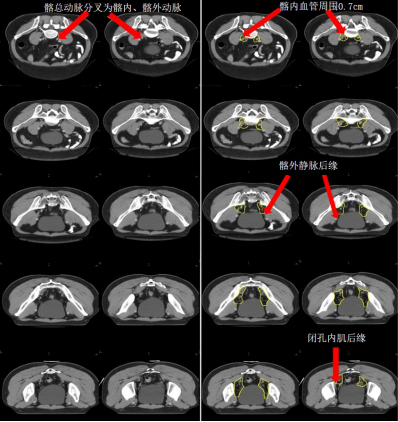

a) GTV(紅色)通過對比定位 MR 圖像,在 CT 定位圖像完成 GTV 的勾畫(圖 1)。

圖 1 直腸癌 GTV 勾畫示例